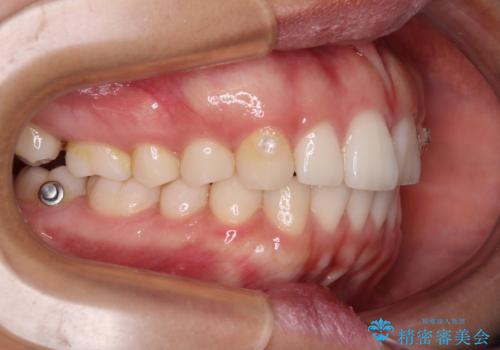

【モニター】突出した前歯 補助装置を併用したインビザライン矯正

- 上下前歯が非接触となり、前方に突出していることを気にして来院された患者様です。

咬合力が強く、全体的に歯がすり減っているため、インビザライン単独での上顎歯列移動は困難と判断し、補助装置により上顎歯列を後方移動させ、その後インビザラインにて仕上げていくこととしました。

補助装置なしでも改善できる可能性はありましたが、補助装置で確実性を上げ、短期間できっちりと仕上げることができました。